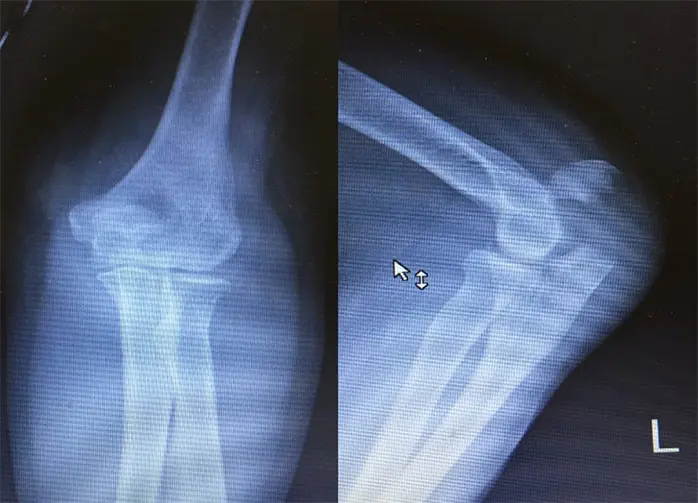

左肘レントゲン

左肘頭骨折認める(Muller AO分類21-C1)